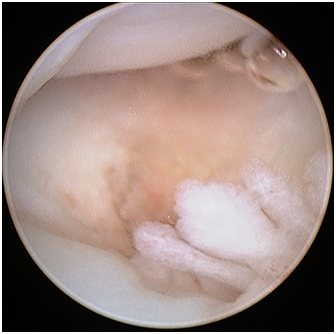

Radio-carpal arthroscopy was done with the 3-4 (between the 3rd and 4th dorsal extensor compartments) portal as the viewing portal and the 4-5 (between the 4th and 5th dorsal extensor compartment) portal as the working portal. The joint was very difficult to scope due to the findings of a “snowstorm” of fibrotic plica bands (Figure 1), thickened synovium covering the TFCC (Figure 2) and further synovitis in the ulno-carpal recess (Figure 3). After debriding all these layers of tissues, the TFCC was found to be intact but stretched over the congenitally deformed ulnar head (Figure 4). There was also early stage chondromalacia of the lunate fossa of the radius.

Figure 2 Radio-carpal arthroscopy left wrist (lunate on top, radius at the bottom) with thickened synovium covering the TFCC area in the ulno-carpal compartment seen once the plica bands have been excised.